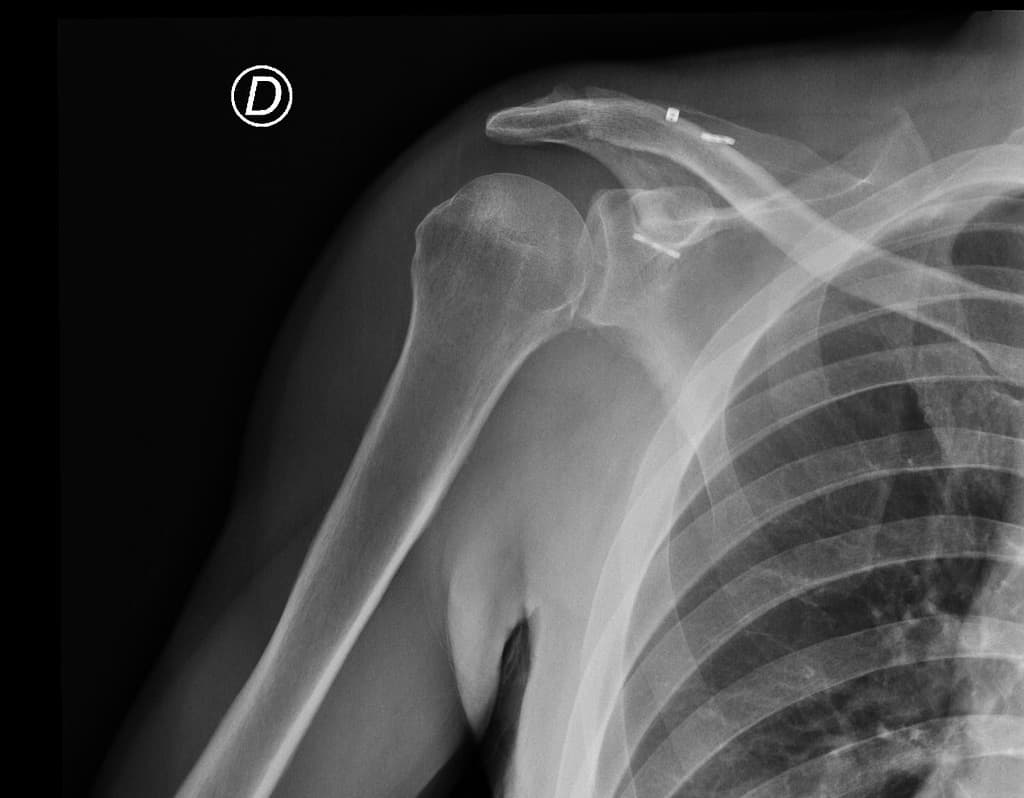

Đau khớp vai phải, sốt

- Có các ổ dịch ngấm thuốc viền (peripherally enhancing collections) xung quanh khớp cùng đòn mỏm cùng phải.

- Các ổ này đi kèm với tín hiệu bất thường ở tủy xương trong mỏm cùng (acromion) và đầu xương đòn (distal clavicle), cùng với các ổ ăn mòn vỏ xương (cortical erosions) ở xương đòn.

Acromioclavicular Joint Dislocation with Tightrope Fixation (Trật khớp cùng đòn với cố định bằng Tightrope)